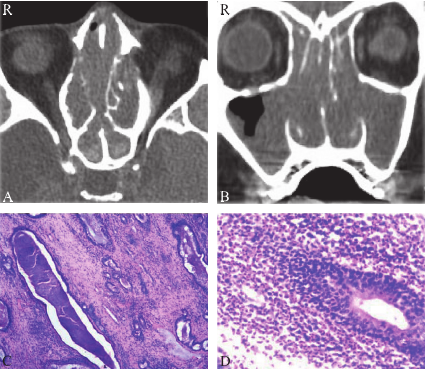

患者,男,79岁。因双侧鼻塞伴流清涕3周余于2016-03-27入院。专科检查:双侧鼻腔可见半透明荔枝肉样新生物,表面光滑,质软,触之不易出血,麻黄素不能使其收缩,鼻道内有大量黏脓样分泌物,鼻窦区无压痛。鼻窦CT平扫

片示:全组鼻窦及双侧鼻腔内炎症表现(图1A、B)。既往史:40年前发现有鼻-鼻窦炎鼻息肉,有多次鼻息肉手术史,最近一次鼻息肉手术为2年前;支气管哮喘

解痉平喘治疗,患者症状缓解。肺部X线片示:两肺纹理增多,主动脉硬化。外周血嗜酸性粒细胞计数0(正常参考值0~0.5×109/L),嗜酸性粒细胞百分率为0.3%(正常参考值0.4%~8%),白细胞介素8为145 pg/ml(正常参考值<62 pg/ml),总补体51.2 IU/ml(正常参考值25~50 IU/ml)。患者在全麻下行鼻内镜下双鼻息肉摘除术+鼻窦开放术。手术中见双侧鼻腔及中鼻道布满半透明荔枝肉样物,表面有黏脓样分泌物,双侧鼻腔解剖结构不清晰,呈鼻窦术后状态,双侧上颌窦窦内有大量黏脓,手术扩大双侧上颌窦、筛窦、额窦以及蝶窦,摘除息肉,吸除窦内黏脓。组织学病理学检查(图1C、D):双鼻腔新生物,符合鼻息肉。免疫组织化学结果:LCA(+少量),CK7(+),CD138(-)。出院诊断:阿司匹林耐受不良三联征(AIT)。

图1 鼻窦CT,A 轴位,B 冠状位,全组鼻窦炎及鼻息肉;C 鼻息肉组织,基底细胞增生,HE×40;D 鼻息肉组织,大量嗜酸性粒细胞浸润,HE×200